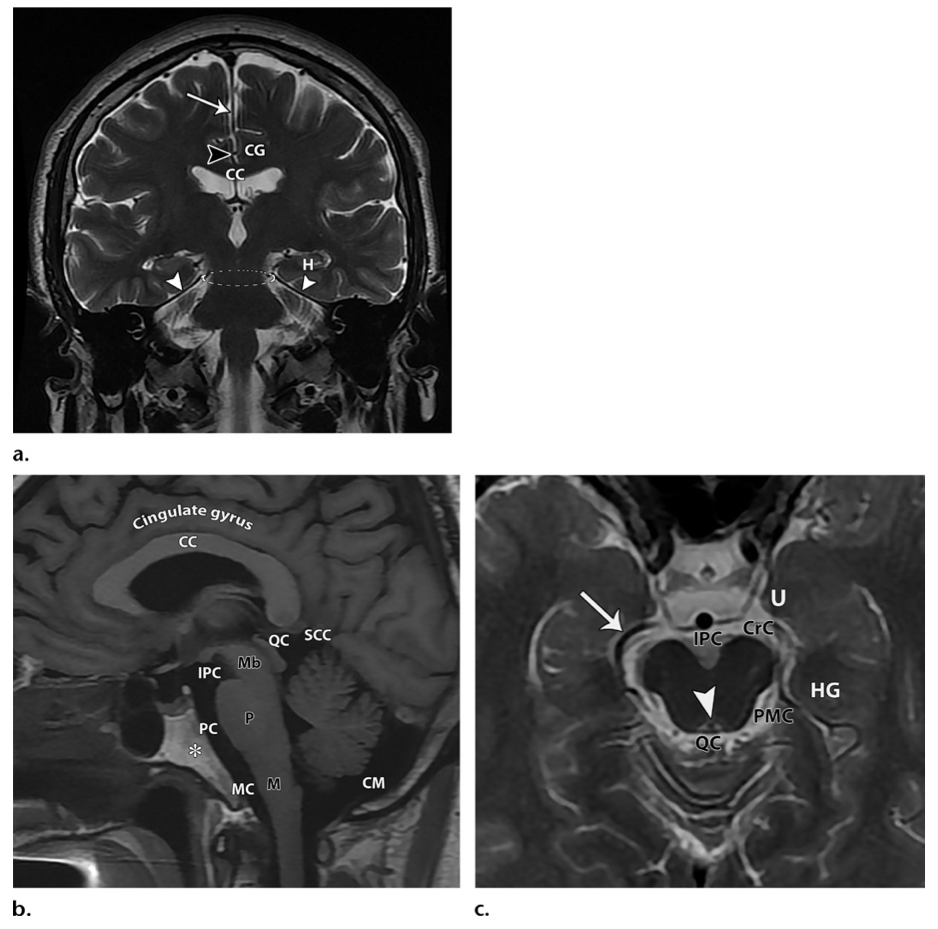

Anatomie vasculaire de l'artère cérébrale antérieure

Anatomie segmentaire :

Source de l'illustration

• A1 : segment horizontal ou pré-communicatante

• origine : terminaison carotidienne ;

• terminaison : au niveau de l'artère communicante antérieure (ACOM) ;

• A2 : segment vertical ou post-communicante ou infracallosal

• origine : au niveau de l'artère communicante antérieure (ACOM) ;

• trajet : le long du rostre du corps calleux ;

• terminaison : au niveau du genou du corps calleux ou à l'origine de l'artère callosomarginale ;

• A3 : segment précallosal

• origine : au niveau du genou du corps calleux ou à l'origine de l'artère callosomarginale ;

• terminaison : lorsque l'artère tourne postérieurement au dessus du corps calleux ;

• A4 : segment supracallosal

• au dessus du corps du corps calleux antérieurement au plan de la suture coronale ;

• A5 : ​segment postcallosal

• au dessus du corps du corps calleux postérieurement au plan de la suture coronale.

NB : artère péricalleuse = partie de l'ACA à partir de A2 ou de A3 (controverse).